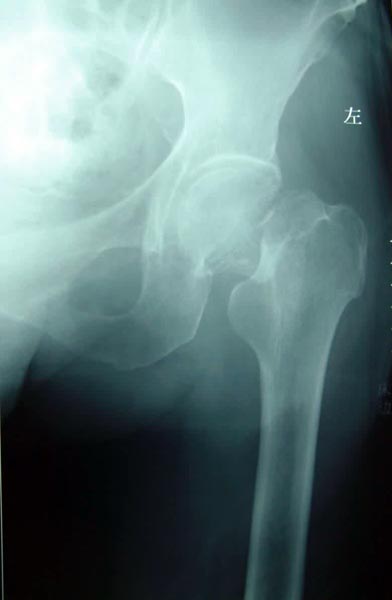

患者82岁,男性,股骨粗隆间粉碎骨折,伴有冠心病、骨质疏松。

采用小切口微创双极人工股骨头置换术置换术,骨折块用钢丝固定。

术后5天下地活动,恢复满意。